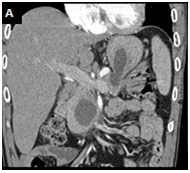

A 46-year-old male, with an alcohol-induced chronic pancreatitis, was admitted with epigastric pain. Laboratory data revealed an aspartate aminotransferase level of 98 IU/L (normal < 40), an alanine aminotransferase level of 85 U/L (normal <60) and a normal serum amylase level. Abdominal contrast enhanced computed tomography (CT) scan showed multiple pancreatic pseudocysts formations and a cystic lesion with 5,9 x 2,5 cm in diameter in the pancreatic head extending to the gastric wall which had an almost entirely intraparietal location Figure 1(A). Upper gastrointestinal endoscopy revealed bulging of the wall in the posterior portion of the gastric body, whose study by endoscopic ultrasonography confirmed the presence of a gastric intramural pseudocyst, with 55 mm in largest diameter, and with solid waste Figure 1(B). The pain resolved spontaneously, and therefore the patient was maintained on surveillance. Three months later abdominal CT showedspontaneous drainage of the intramural pseudocyst Figure 1(C).

Figure 1C Abdominal-CT scan: The gastric intramural pseudocyst had completely disappeared.